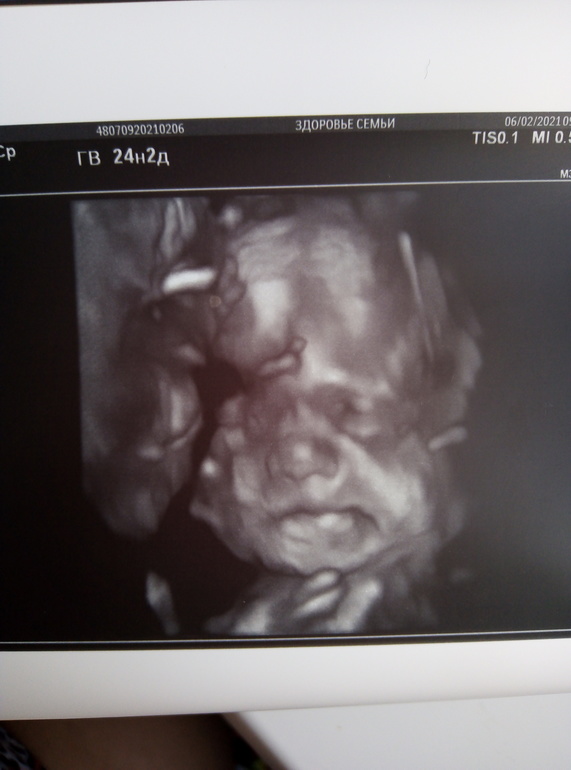

25 НЕДЕЛЬКА фотопуз + УЗИ❤️

Стартовала 25 неделя, как же быстро летит время, сгонял на доплер, заодно посмотрели дочу в 3д, ну и всё остальное быстро глянули, всё хорошо тьфу тьфу, волосы говорит длинные уже у вашей принцессы, я аж удивилась, показала мне прям волосы на голове ёжик такой прям, а фото в 3д боже такой гномик шладкий и тут я поняла что мы вылитый папа))))